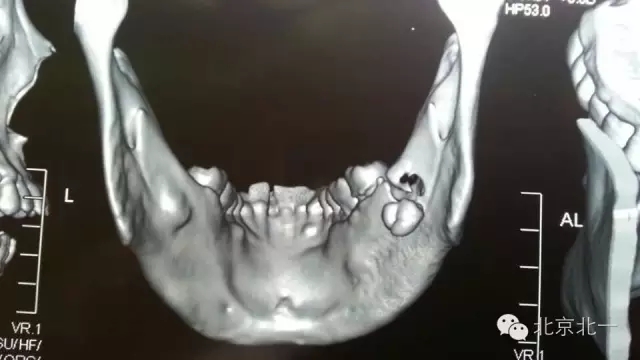

圖一:全景片可見下頜骨下緣高密度影像,清晰可見。

640.webp (5).jpg